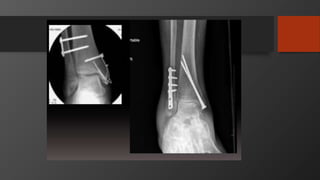

Ankle Fractures

Imaging

• AP, Lateral

• Mortise view

• CT scan

• Especially posterior malleolus

Treatment

• Isolated lateral malleolus fractures

• Isolated medial malleolus fractures

• Bimalleolar fractures

• Posterior malleolus fractures

Syndesmosis injury

Special consideration

• Diabetics

• Enhance fixation

• Delay weight-bearing for 8-12 wks